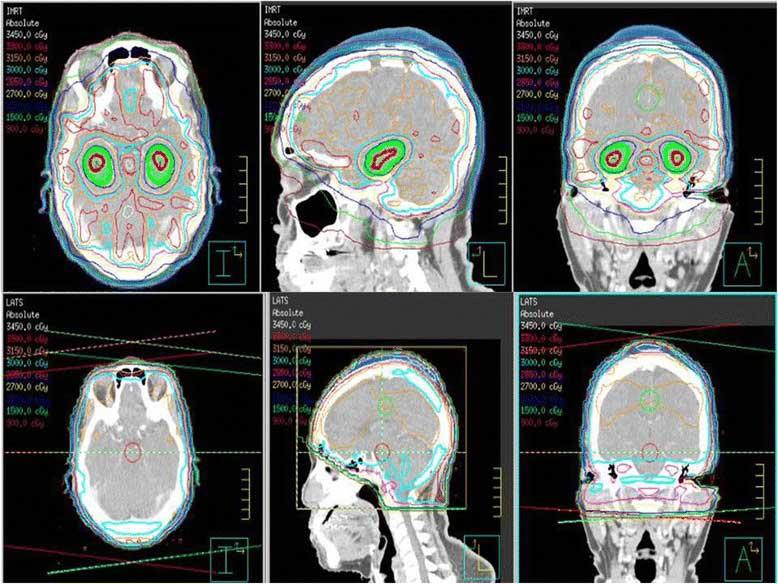

An image comparing whole brain radiation therapy that avoids the hippocampus with standard whole brain radiation therapy.

Whole brain radiation therapy that avoids the hippocampus (top 3 panels, green shaded area) compared with standard whole brain radiation therapy (bottom 3 panels).

Credit: Radiat Oncol Nov. 2015. doi: 10.1186/s13014-015-0555-9 CC BY 4.0